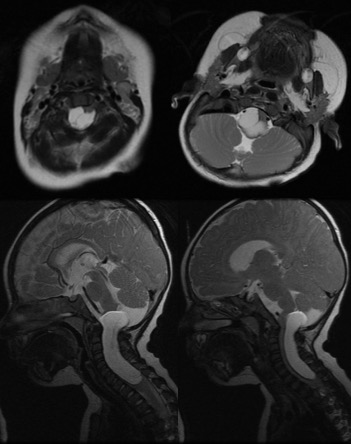

l’hydrocéphalie

il s’agit d’un mode de révélation non exceptionnel, parfois liée à

- une tumeur volumineuse

- ou avec dissémination méningée

- parfois associée à une pseudo-tumeur de petite taille, de nature vasculaire ou inflammatoire.